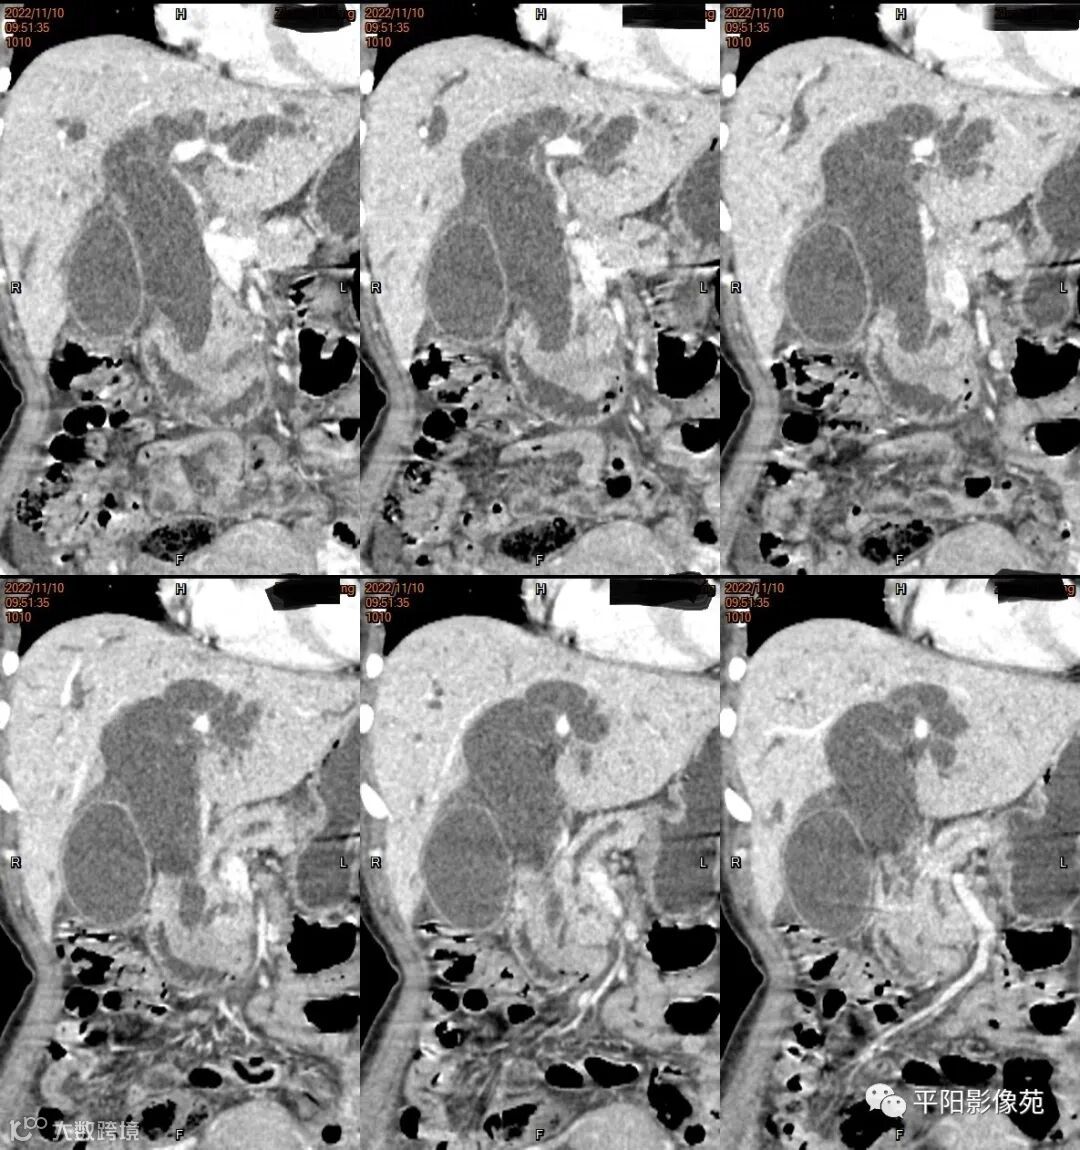

影像学检查

CT

影像表现: